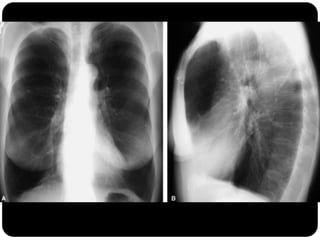

Atelectasia do Lobo Sup. D. (compare com slide

anterior que era consolidação de LSD!)

Atelectasia do LoboSup. D. (compare com slide anterior que era consolidação de LSD!)